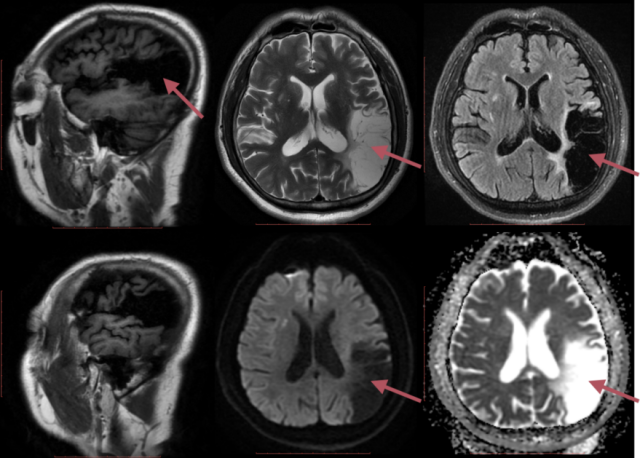

在一个阳光明媚的下午,我和往常一样,下楼溜弯,回家喂鸟,整两盘小菜,刚坐下喝了一口小酒就眼前一片黑暗,什么都不知道了。一向「健康」的我突然躺在地上一动不动,可把我儿子吓坏了,赶紧把我送到医院,医院检查结果竟然显示我左侧大脑大面积脑梗死,又做了头颈部 CTA 检查,结果发现头颈部血管并没有明显狭窄,那这是怎么回事?

经过进一步检查发现,发病原因竟然是升主动脉内长了「肿瘤」?之后来到安贞医院完善主动脉 CTA 检查,结果确实发现在升主动脉腔内漂着一个「肿瘤」,长径大约 4 cm,出血脑梗死可能就是这个「肿瘤」部分脱落导致血管梗塞。